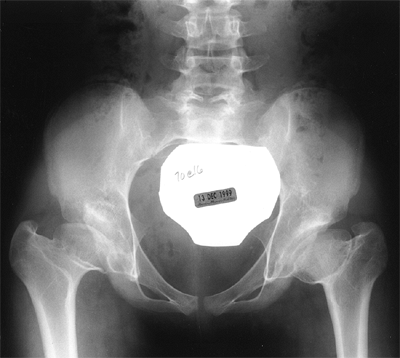

All subluxated hips (i.e., those in which there is some contact between

dysplastic. On film, the major difference between radiographic dysplasia and radiographic subluxation is determined by the integrity of the Shenton line. In radiographic subluxation,

the Shenton line is disrupted and the femoral head is superiorly,

laterally, or superolaterally displaced from the medial wall of the

acetabulum. In radiographic dysplasia, the normal Shenton line relation is intact (57,66,211,212) (Fig. 24.23).

In the literature describing the natural history of DDH, these two

radiographic and clinical entities are often not separated. Moreover,

secondary degenerative changes may convert a radiographically dysplastic hip into a radiographically subluxated hip (202,204,208,209,212,213,214) (Figs. 24.24 and 24.25).

Figure 24.25 A: Anteroposterior view of a 4-month-old girl with left hip dislocation and right hip subluxation. B: Abduction view. C: Abduction view at 7 months of age, 3 months after closed treatment. D: Anteroposterior view at 7 months of age, 3 months after closed treatment. E: Anteroposterior view at 7 years of age. Note the mild anatomic dysplasia of both hips. F:

Anteroposterior view at 15 years of age. Note the bilateral anatomic dysplasia. The right hip is radiographically dysplastic, and the left hip is radiographically subluxated. |